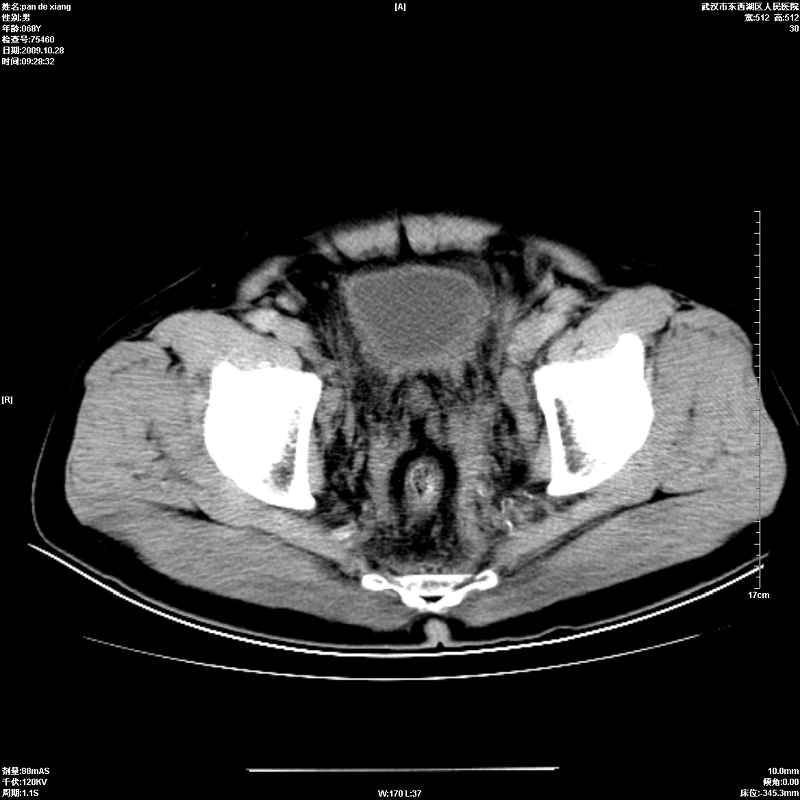

以下是引用杀毒软件在2009-10-28 20:41:00的发言:[br]结合临床考虑---白血病双肾改变或淋巴瘤。

以下是引用zxl51642在2009-10-29 9:59:00的发言:[br]结合临床“单克隆免疫球蛋白血症”,考虑双肾为继发损害并肾功能不全(尿中大量igg及少量iga、igm等大分子免疫球蛋白滤出所致继发损害),椎前软组织肿块为髓外造血。与浆细胞瘤有区别,平扫时有战友说的很清楚。